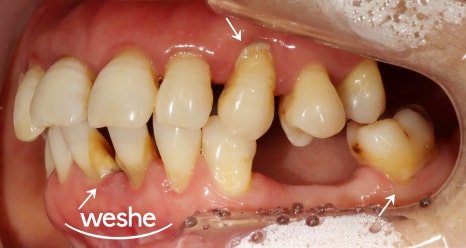

송정역 치과 치료 기간 : 2023.05.12~2024.02.14

치아가 앞쪽으로 밀려나거나

부채꼴 모양으로 벌어지는

현상이 대표적이며,

치간이개와 치주질환이

동시에 나타나는 경우,

정확한 진단을 위해서는

체계적인 검사가 필요합니다.

육안으로 확인되는 치아 간격의 정도와

잇몸의 염증 상태를 1차적으로 평가한 후,